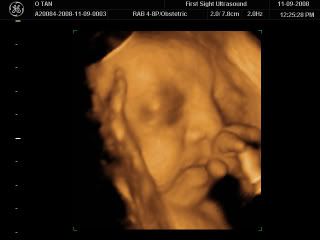

Baby Caleb all annoyed by us poking him with the Ultrasound scope! Giving a little yawn and all prepared to turn away from us!!!